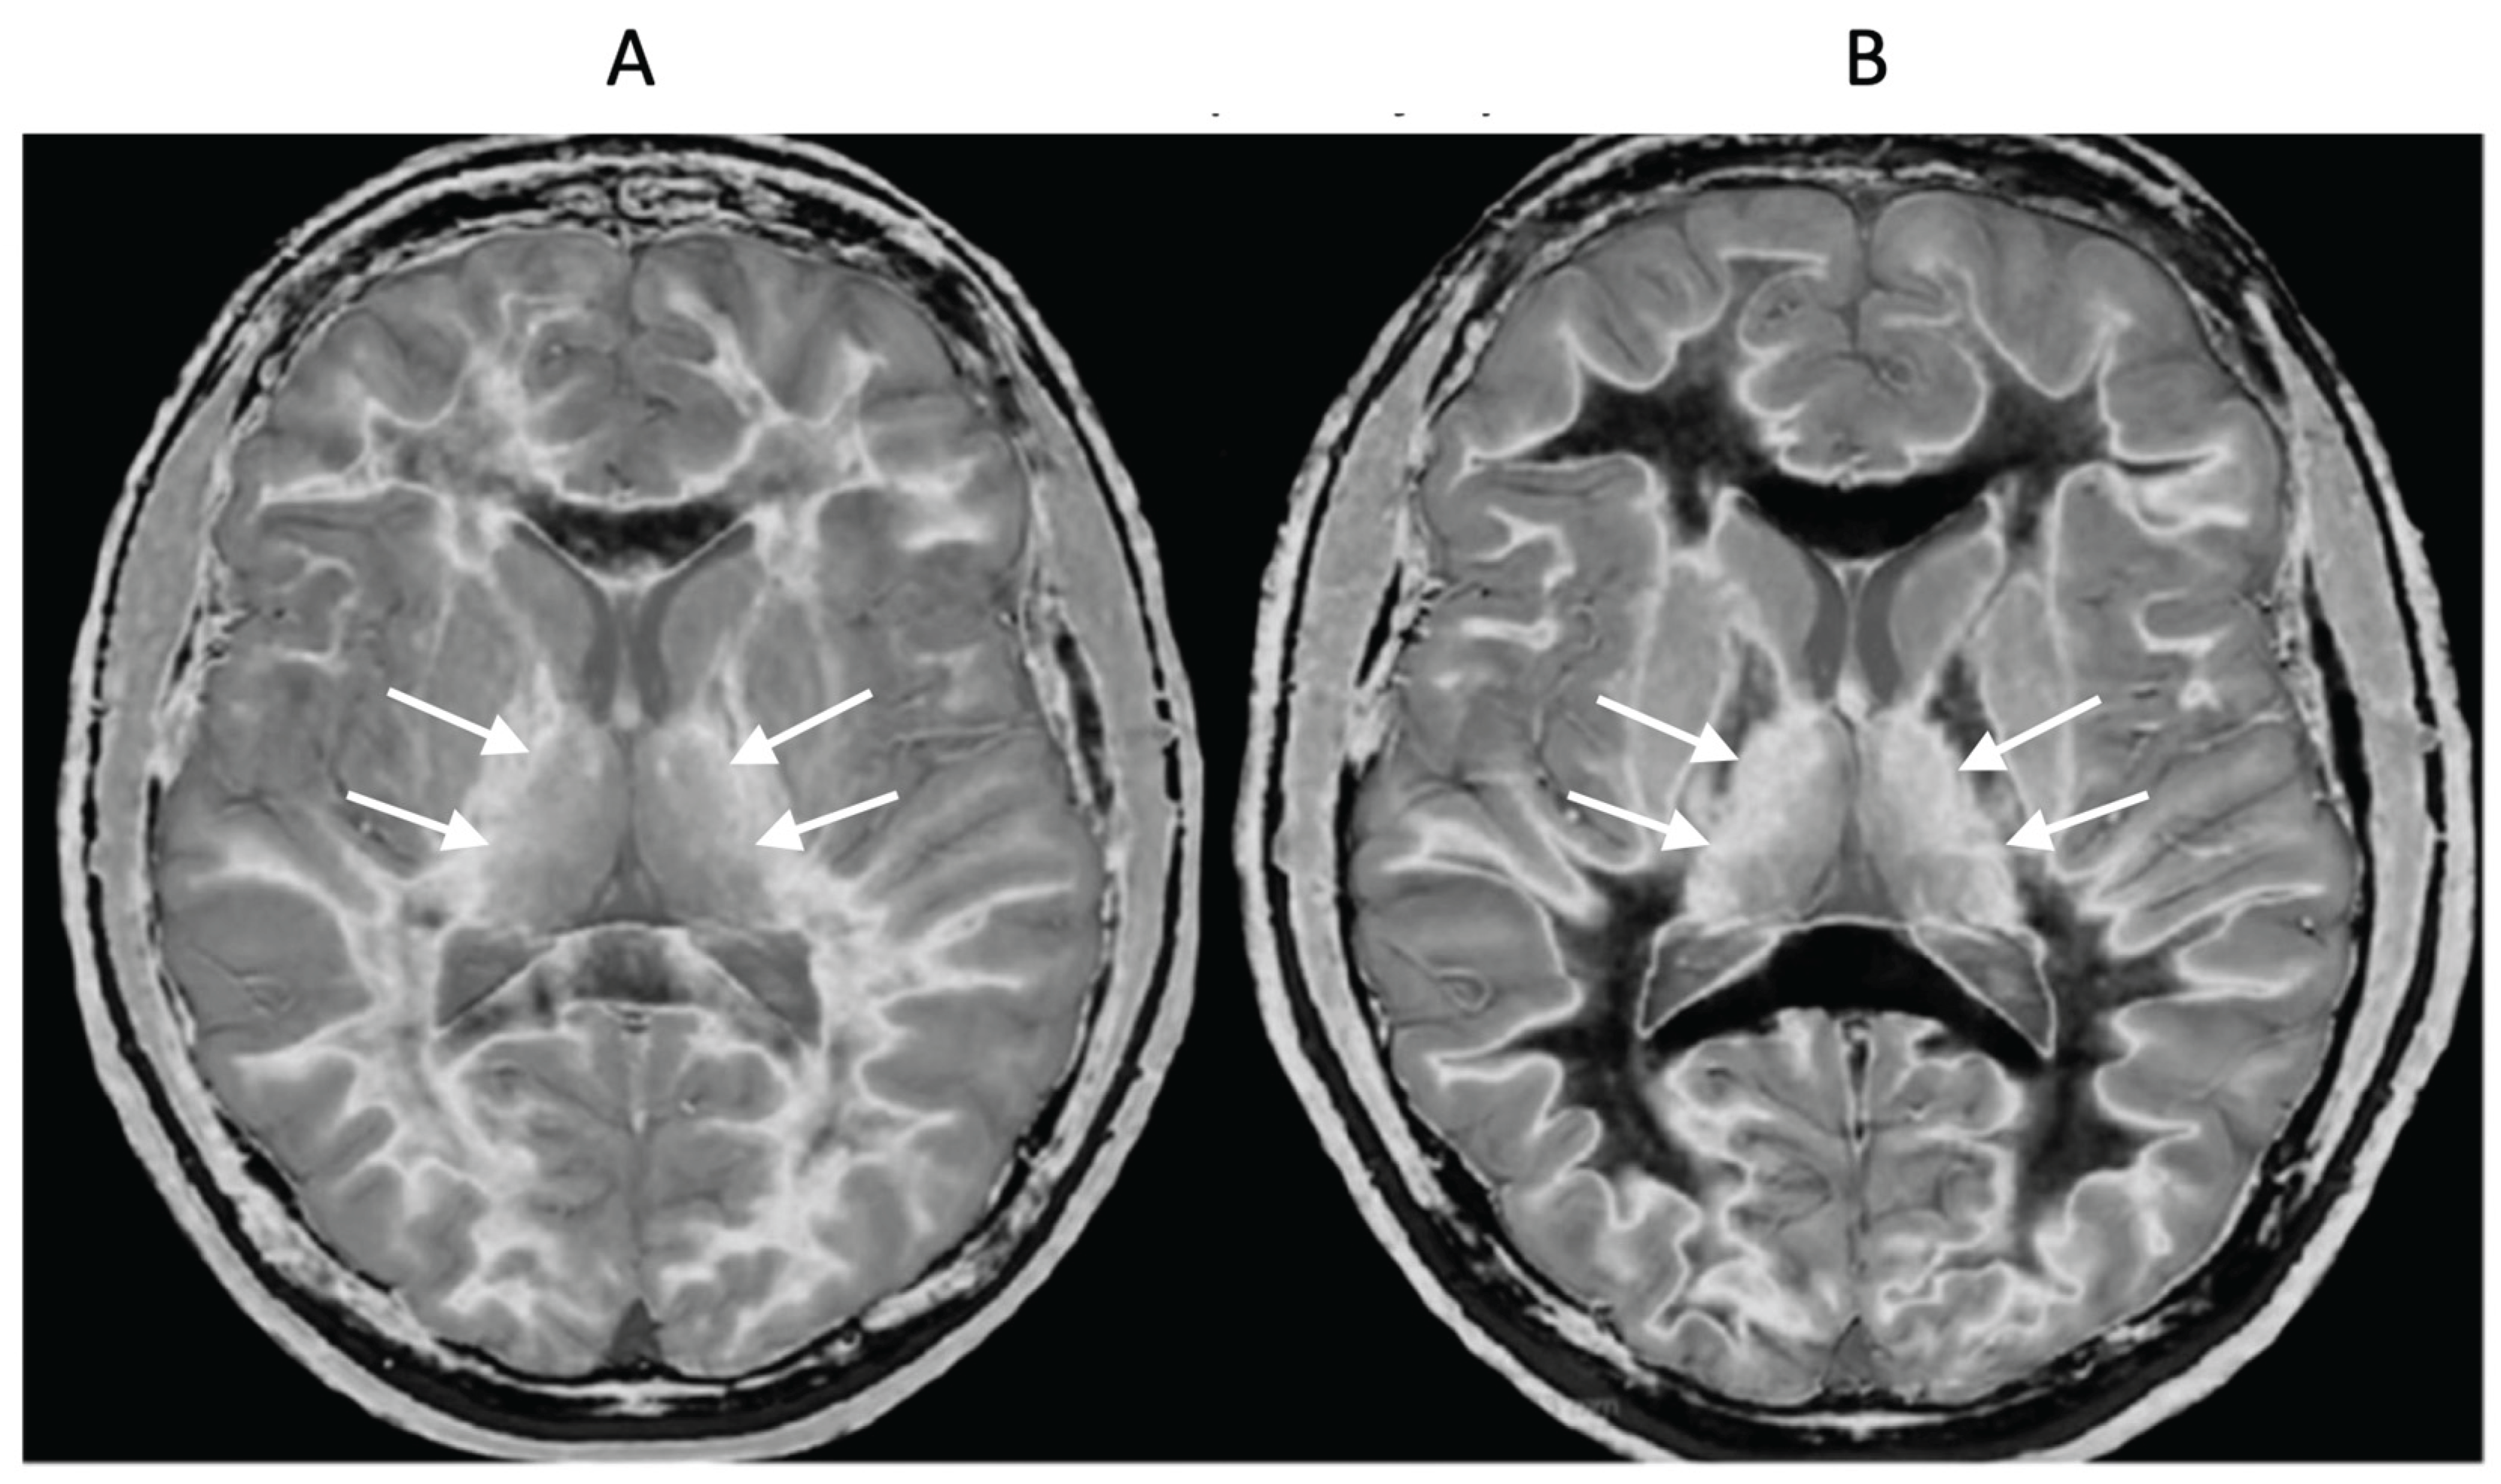

18-year-old patient with mTBI 21h (A) and 64h (B) post injury imaged with the same narrow mD dSIR sequence. In (A) the patient shows a whiteout sign (grade 4 out of 5) with high signal in most of the white matter in the cerebral hemispheres except for the anterior and posterior central corpus callosum. The posterior limb of the internal capsule is high signal. The thalami show low internal contrast from medial to lateral (arrows on lateral margins of the thalami). There is also low external contrast between the lateral margins of the thalami and the adjacent posterior limbs of the internal capsule. On the follow up examination at 64h (B) the whiteout sign has resolved and there is low signal in the white matter including the posterior limbs of the internal capsule (except for the corticospinal tracts). The thalami now show high internal contrast from medial to lateral (arrows on lateral margins of the thalamus) which is the normal appearance at this age. There is now also very high external contrast between the lateral margin of the thalamus and the adjacent posterior limb of the internal capsule. Image (A) shows the grayout sign which is a reduction in the high contrast between the medial and lateral gray matter of the thalamus. The high contrast is restored in (B). No abnormality was seen on the corresponding T2-FLAIR images obtained at both time points.